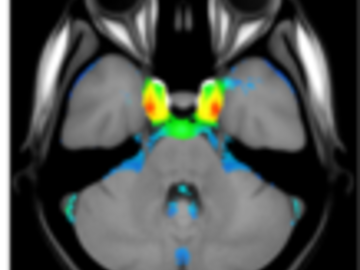

A statistical atlas of cerebral arteries

Magnetic resonance angiography (MRA) can capture the variation of cerebral arteries with high spatial resolution. These measurements include valuable information about the morphology, geometry, and density of brain arteries, which may be useful to identify risk factors for cerebrovascular and neurological diseases at an early time point. However, this requires knowledge about the distribution and morphology of vessels in healthy subjects. the statistical arterial brain atlas described in this work is a free and public neuroimaging resource that can be used to identify vascular morphological changes. The atlas was generated based on 544 freely available multi-center MRA and T1-weighted MRI datasets. the arteries were automatically segmented in each MRA dataset and used for vessel radius quantification. The binary segmentation and vessel size information were non-linearly registered to the MNI brain atlas using the T1-weighted MRI datasets to construct atlases of artery occurrence probability, mean artery radius, and artery radius standard deviation. This public neuroimaging resource improves the understanding of the distribution and size of arteries in the healthy human brain.

The statistical atlas consists of four image files in the niftii format and in MNI reference space (0.5 mm^3). These files include the TOF MRA average atlas (tofAverage.nii.gz), the vessel probability atlas (vesselProbabilities.nii.gz [in %]), the mean artery radius atlas (vesselRadius.nii.gz [in mm]), and the standard deviation of the artery radius atlas (vesselRadiusStd.nii.gz [in mm]). All images are saved using float values. The TOF MRA and T1-weighted datasets used for atlas generation can be downloaded from the original sources.